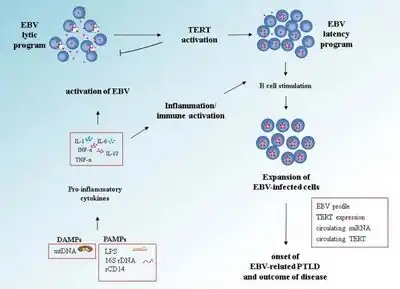

| Pathogenetic mechanisms of early onset EBV-related PTLD[1] | |

The disease is an uncontrolled proliferation of B cell lymphocytes latently infected with Epstein–Barr virus (EBV).[2][3] Production of an interleukin-10, an endogenous, pro-regulatory cytokine, has also been implicated.

In immunocompetent patients, Epstein-Barr virus can cause infectious mononucleosis in adolescents, which is otherwise asymptomatic in children during their childhood. However, in immunosuppressed transplant patients, the lack of T-cell immunosurveillance can lead to the proliferation of these EBV-infected B-lymphocytes.

However, calcineurin inhibitors (tacrolimus and ciclosporin), used as immunosuppressants in organ transplantation inhibit T cell function, and can prevent the control of the B cell proliferation.